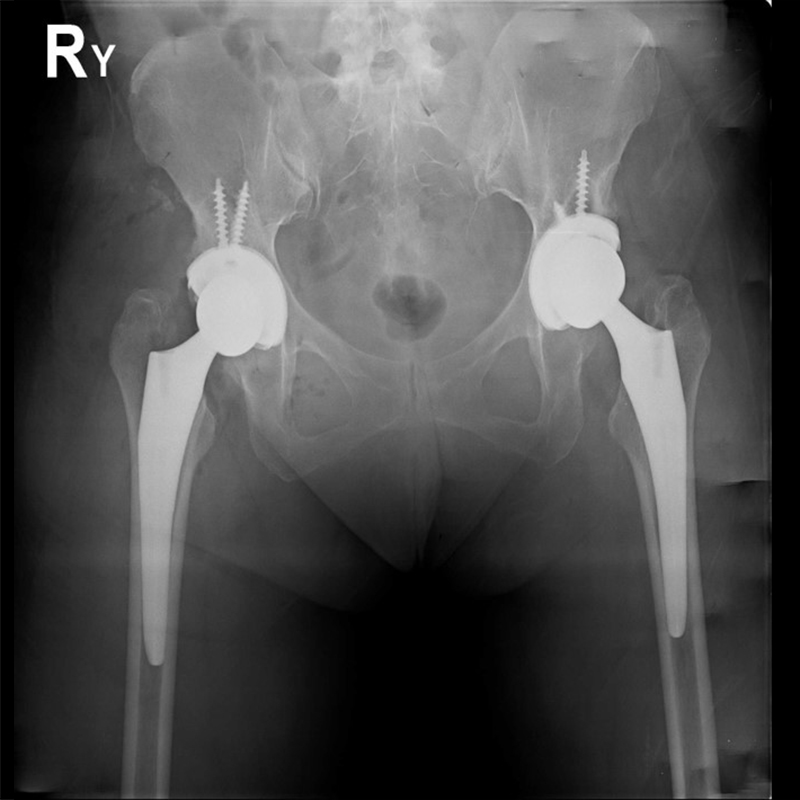

機器手臂手術 首頁 案例分享 髖關節手術 機器手臂手術 72歲 楊女士 退化性關節炎 術前 術後 60歲 彭先生骨股頭壞死 術前 術後 53歲 王女士退化性關節炎(DDH先天發育不全 CROWE TYPE 2) 術前 術後 83歲林女士退化性關節炎 術前 術後 83歲林女士退化性關節炎 術前 術後 楊女士 70歲 術前 術後 蔡女士 60歲 術前 術後